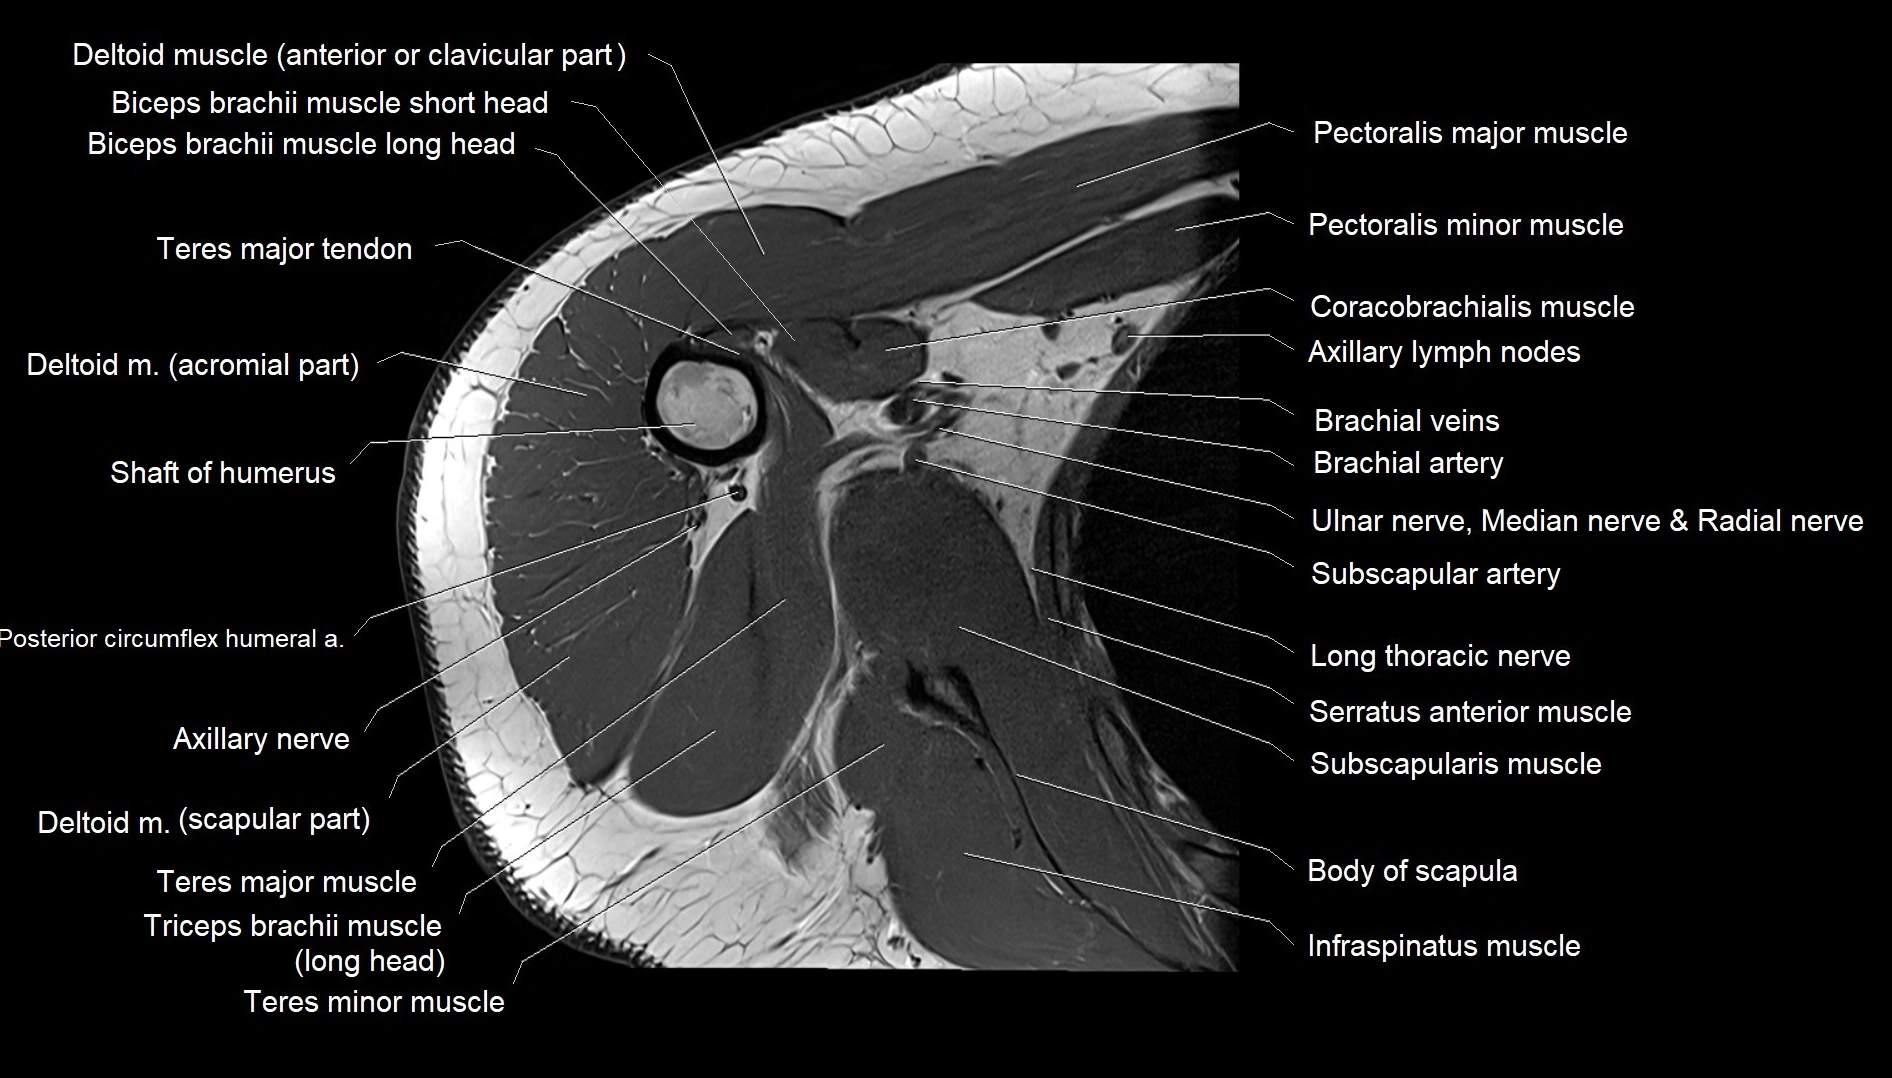

MRI images

image